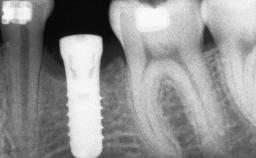

Iliac and Calvarial Bone Blocks for Onlay Grafting of a Severely Resorbed Edentulous Maxilla

A 45-year-old woman with a completely edentulous maxilla was referred to evaluate the possibility of rehabilitation with an implant-supported prosthesis. This patient was healthy and a non-smoker. She had been wearing a maxillary complete denture opposing a natural mandibular dentition since her twenties. This situation had resulted in progressive resorption of the alveolar ridge, repeatedly creating a need for relining the denture. Twenty years later, despite multiple adaptations and the use of “glues” the denture was unstable and causing the patient psychological and functional discomfort.

Type of Implants Reduced-Diameter|Two-Piece

Bone Augmentation Horizontal|Sinus Floor Elevation|Staged|Vertical